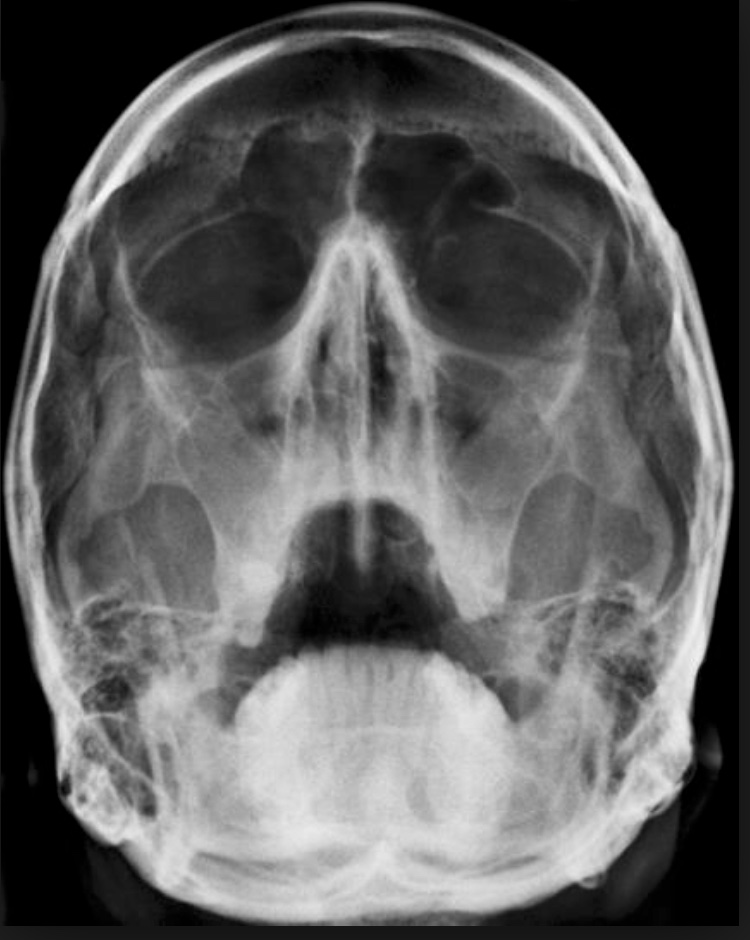

Broken Nose X Ray

What Does A Broken Nose Look Like On Xray These findings include persistent epistaxis or rhinorrhea, septal hematomas, visual disturbances, compound fractures or suspected facial fracture, or severe headache,. A nose fracture involves cracked or broken nasal bones and/or cartilage. He or she may look inside your nasal passage to check for obstruction and further signs of broken bones. You may have swelling and bruising around your nose and under your eyes. Put gentle pressure on the outside of. Ask about how the injury happened; Your doctor will examine not only your nose, but also the surrounding areas including your eyes, jaw, and teeth, and will look for bruising, cuts,. Your nose may look crooked, and you may have trouble. These findings include persistent epistaxis or rhinorrhea, septal hematomas, visual disturbances, compound fractures or suspected facial fracture, or severe headache,. Nasal fracture treatments include manual realignment and — in severe. To find out if your nose is broken, your doctor probably will: The radiologist should look for abnormalities of the nasal septum and arch, keeping in mind areas of relative weakness. Marked deviation, displacement with sharp.